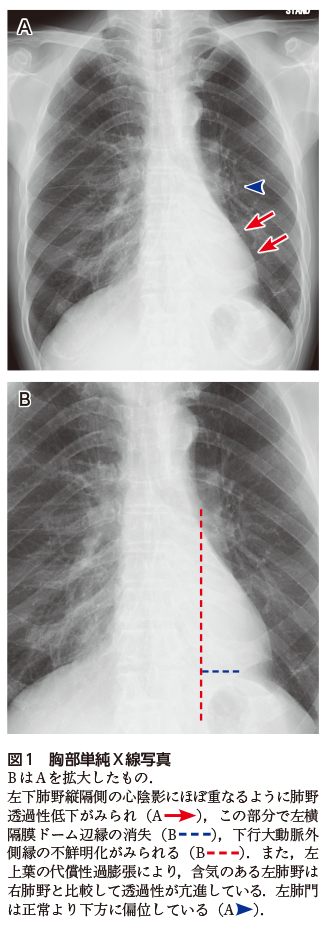

胸部造影CTでは左下葉の中枢側に腫瘍と思われる領域が認められ(図2A),左下葉が無気肺となっている(図2A).両者は一塊となっており区別がつきにくいが,無気肺部分は腫瘍より造影効果がやや高く,内部には気管支内粘液栓を示す樹枝状の造影不良域がみられる(図2B).

図2